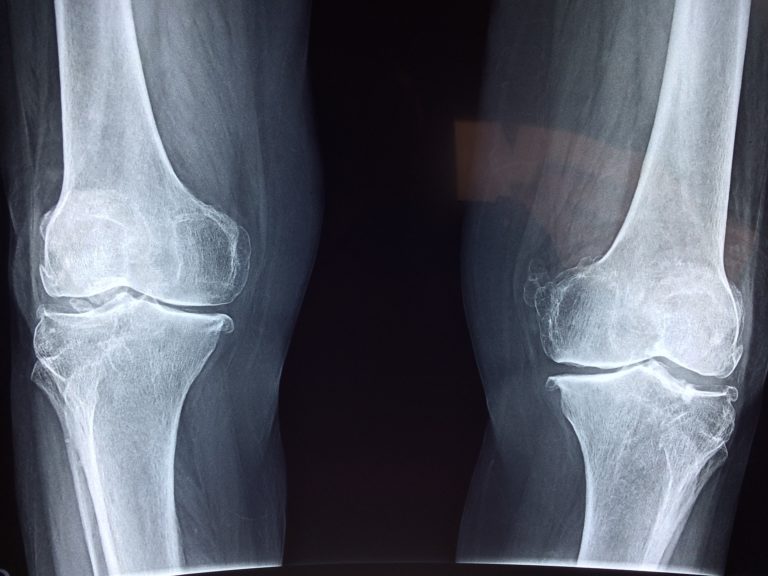

Odkryj natychmiastową ulgę na bolące kolana: Po prostu nałóż i śpij spokojnie, nawet gdy ból stawów wydawał się nie do zniesienia.

Każdemu cierpiącemu na bóle stawów i kości polecam ten lek. Jest on szczególnie efektywny w przypadku reumatyzmu czy innych stanów zapalnych.

Dodatkowo, oto kilka porad na obrzęki i ból kolan: